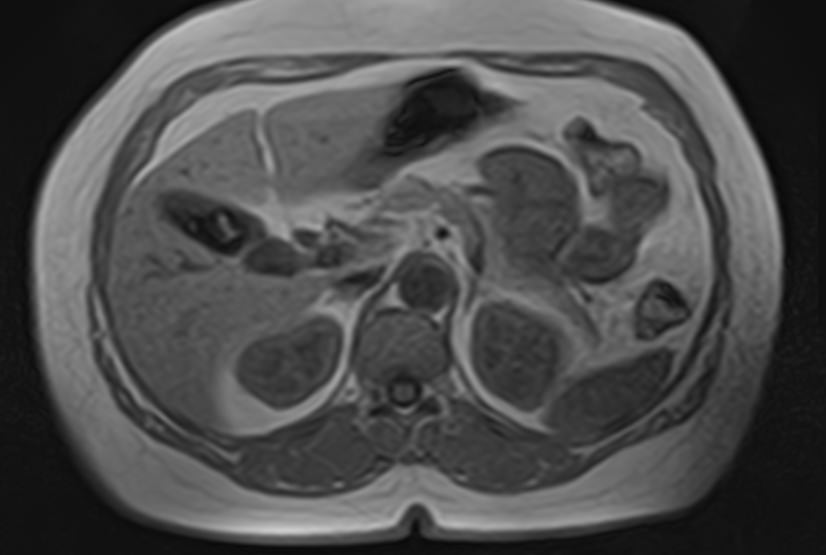

МРТ забрюшинного пространства является наиболее информативным, безопасным и доступным методом исследования, который позволяет оценить состояние органов, расположенных в данной анатомической зоне (почки, надпочечники, мочеточники), выявить возможные патологические процессы.

В клинике «Доступная медицина» установлен новейший высокопольный томограф экспертного уровня TOSHIBA VANTAGE TITAN 1,5 Тесла, на котором выполняется обследование органов забрюшинного пространства. За счет высокой индукции магнитного поля аппарат при сканировании создает изображения на плоскости превосходной четкости, затем с помощью компьютерных приложений данные преобразуются в изображения трехмерного формата, что обеспечивает точность и достоверность диагностики.

МРТ брюшного и забрюшинного пространства направлено на определение состояния нескольких органов, по результатам диагностики визуализируют:

- Почки. С помощью магнитно-резонансной томографии удается диагностировать структурные изменения. Аномалии развития, воспалительные процессы, изменение нормального расположения в забрюшинном пространстве.

- Надпочечники. Парный орган эндокринной системы. Из-за особенностей анатомии, строения, трудно визуализируются прочими способами. МРТ позволяет получить детальную картину изменений надпочечников.

- Аорта и нижняя полая вена. В рамках диагностики структурных патологий.

- Мочеточники. Часть мочевыделительного тракта. Из-за малого диаметра и особенностей строения, визуализируются с трудом. Томография — основной способ диагностики патологических процессов.